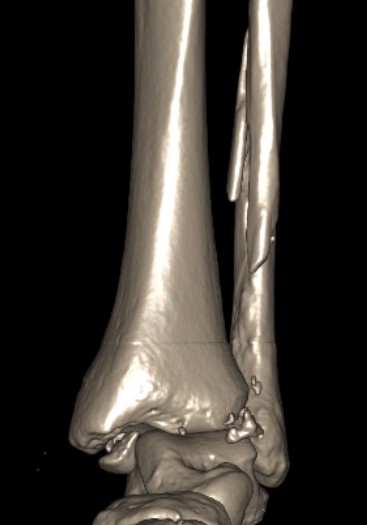

Tri-Malleolar Fracture

Definition

Lateral malleolus + medial malleolus + posterior malleolus

Posterolateral approach

- prone or lateral

- ORIF fibula + posterior malleolus

- move patient to supine to ORIF medial malleolus